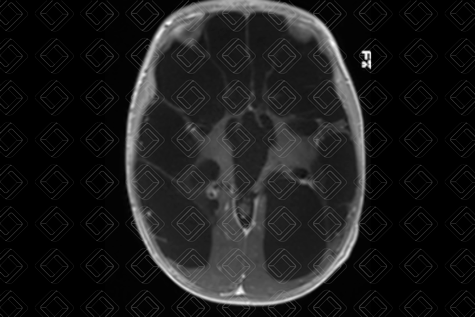

Texto alternativo para a imagem Figura 2. Créditos: Dra. Elazir Mota - Rio de Janeiro/RJ

Descrição das figuras 1, 2 e 3: Ressonância magnética de crânio com sequência CISS. Uma sequência ponderada em T2, cujas imagens císticas apresentam sinal elevado (seta vermelha) e imagens ponderadas em T1 nos planos axial e sagital. É possível observar as múltiplas imagens císticas ocupando a região cortical e de substância branca, predominando no compartimento supratentorial e poupando cerebelo e tronco (setas amarelas).

• Múltiplas cavidades císticas, de tamanhos variados, envolvendo substância branca e região córtico-subcortical;

• Dilatação ex-vacuum do sistema ventricular por atrofia do parênquima cerebral;